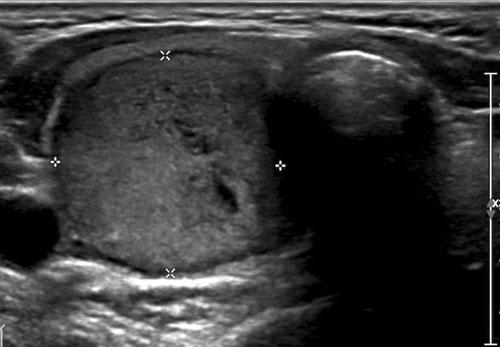

Trường hợp 3

Quan sát hình ảnh và xác định điểm TI-RADS.

Cuộn hình ảnh để xem điểm TI-RADS.

Đây là một nốt tăng âm.

Điểm TI-RADS: 1 điểm cho độ hồi âm.